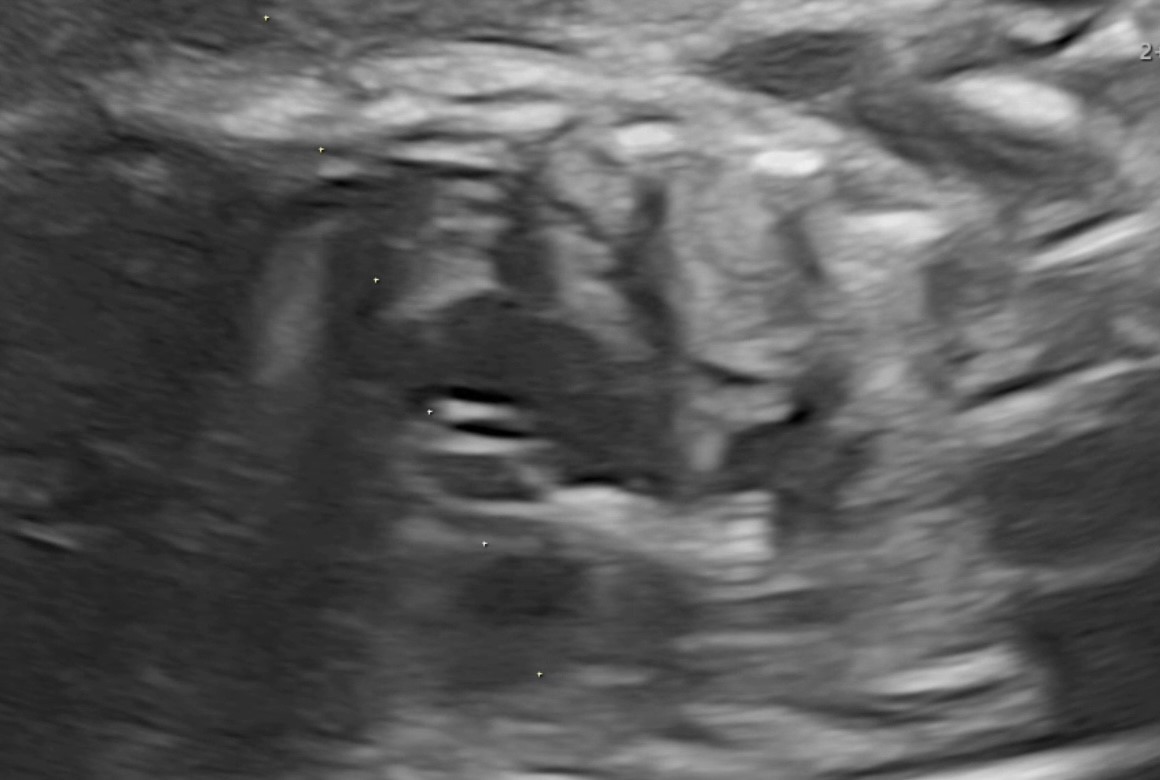

3 a. до выполненной вальвулопластики клапана аорты

По данным ультразвукового исследования после выполненной вальвулопластики клапана аорты и извлечения баллона с иглой отмечается увеличение эффективного отверстия клапана аорты и отсутствие жидкости в полости перикарда.